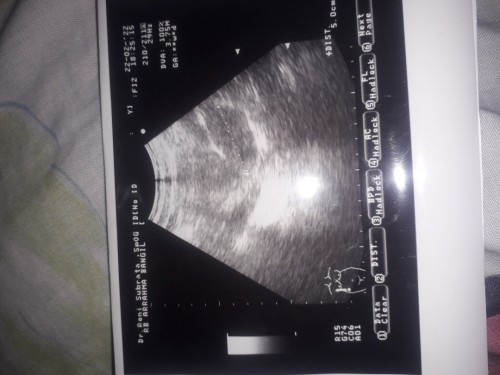

Bun ada yang tau ga ini mksdnya gmna

itu mungkin maksudnya penebalan dinding rahim bun, ada tulisan +DIST. Mohon maaf kalo saya salah. ๐๐ป

ktanya blum kelihatan kantungnya dan ada kistanya